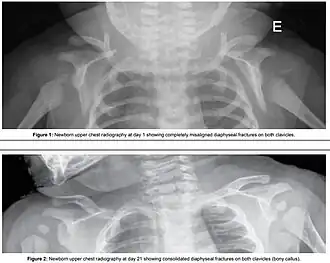

- Clavicular or humeral fractures[9][11]